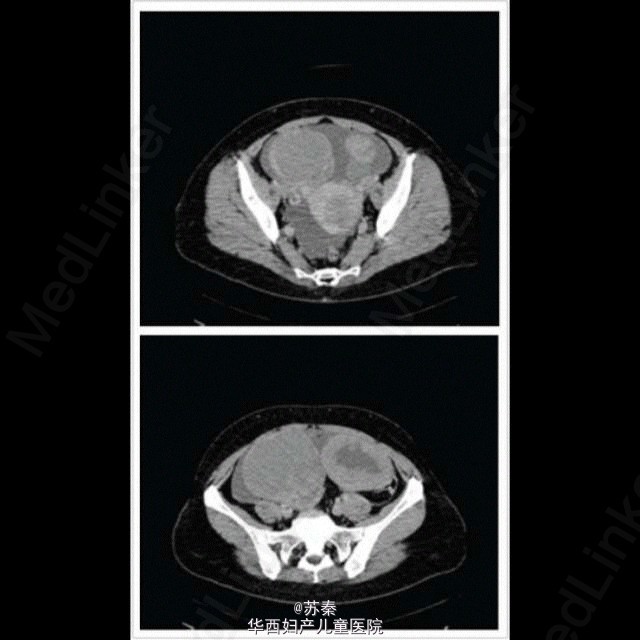

同期子宫内膜间质肉瘤与双侧卵巢腺癌

少见的同期子宫及卵巢癌 来自Olga Caramelo,A Case of Endometrial Stromal Sarcoma with Synchronous Bilateral Adenocarcinoma of Ovary,2012,Acta obstetricia et gynecologica Scandinavica